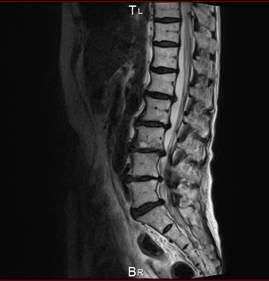

脊柱管狭窄症(腰痛)

脊柱管狭窄症(腰痛)の手術に踏み切った。

「手術で腰にプレートを入れたのですが、以前よりも痛みが増して、前屈みにならないと歩くことすらできない状態になってしまいました。

なんとか仕事は続けていますが、通勤がとにかく大変なんです。長時間立っていられないので、混む電車を避け、何本も早い電車に乗って会社に行っています。医者から『手術すれば治るから』と言われて手術を受けたのにこんな後遺症が残るなんて……後悔しています」

腰痛患者を多数抱える、鍼灸師は、腰の手術についてこう語る。

「最初は手術が成功したと感じても、しばらく経つと必ず何かしら身体に不具合が出てきます。この患者さんの場合は、異物としてのプレートを入れていますので、身体がそれに拒絶反応を起こしてしまったのでしょう。

骨』だと診断し、すぐに手術をする。でも実際は、背骨の下にある仙腸関節に原因がある場合が多いのです。

MRIというものは、背骨のでっぱりや変形はわかっても、そこが痛みの原因であるかどうかを教えてくれるものではない。原因箇所がはっきり分からないまま手術をしてもそれはよくなりません。その意味でも、やはり医者の経験と診断力が肝心なのです」

医療が進歩した現在においても、腰痛の85%は原因不明といわれる。にもかかわらず、大半の医者は画像に見えるものがすべてだと思い、手術をすすめる。